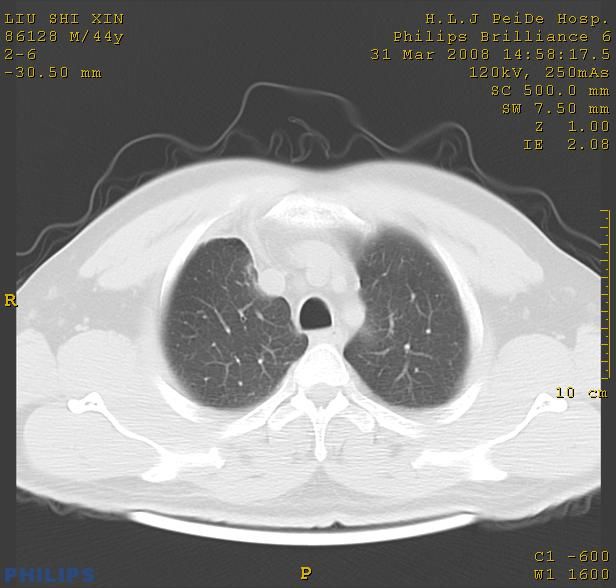

标题: CT13096:请分析胸膜下结节的影像基础是什么 有病理结果 [打印本页]

标题: CT13096:请分析胸膜下结节的影像基础是什么 有病理结果

瘢痕挛缩,胸膜牵拉,血管纠集扭曲,上叶前段支气管显示欠清,周围散在斑片影,以纵隔旁肺癌可能性大。请穿刺检查。

中心型肺癌并阻塞性肺炎、两肺及胸膜多发转移。

结节灶与血管末梢相通象转移灶;小三角状尖部有纤维索是胸膜拉扯征;纵隔旁大片实性影有点状钙化;周围有名显纤维瘢痕征可考虑瘢痕癌

本病例有病理结果是,鳞状上皮癌,胸膜下结节影病现诊断的肿大淋巴结,谢谢大家分析,请问胸膜下结节是肿大淋巴结怎么解释